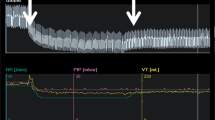

A 35-year-old man was admitted to the ICU with a diagnosis of ARDS secondary to COVID-19. He was sedated and paralyzed while receiving controlled mechanical ventilation with a volume-controlled mode. The baseline total PEEP was 14 cmH2O. Airway driving pressure was 14 cmH2O and exhaled VT was 429 mL with a RR of 2 23 and FiO2 of 0.4. The R/I ratio was calculated as 0.44, suggesting a lower potential for lung recruitment at higher PEEP. A decremental PEEP trial was performed to personalize this patient’s PEEP. The ventilator mode was switched to pressure-control (PC) with a driving pressure (PC above PEEP) set at 15 cmH2O throughout the trial. First, PEEP was increased to 18 cmH2O (time point A on Fig. 1) and maintained for 1 minute. Then PEEP was decreased by increments of 2 cmH2O until a PEEP of 8 cmH2O was achieved, with each PEEP level maintained for 1 minute (time points B through F). Respiratory mechanics and oxygen saturation recorded during each step reported in Table 1.

demonstrates a regional analysis of lung mechanics obtained during the decremental PEEP trial, provided as a diagnostic tool. Alveolar overdistension is represented in orange as a “compliance loss” (C loss HP) that occurred at higher PEEP (more overdistension at time point A (PEEP 18 cmH2O) compared to B (PEEP 16 cmH2O)). Alveolar collapse is represented in white as a “compliance loss” (C loss LP) that occurred at lower PEEP (more collapse at time point F (PEEP 8 cmH2O) compared to E (PEEP 10 cmH2O)). The crossover point representing minimal overdistension and atelectasis was 10 cmH2O (time point E). Below this value, dorsal collapse increased. Above this value, no collapse was detected, but increasing ventral overdistension developed. This example illustrates how EIT might be used as an incentive to reduce PEEP and optimize regional lung mechanics in a patient with ARDS